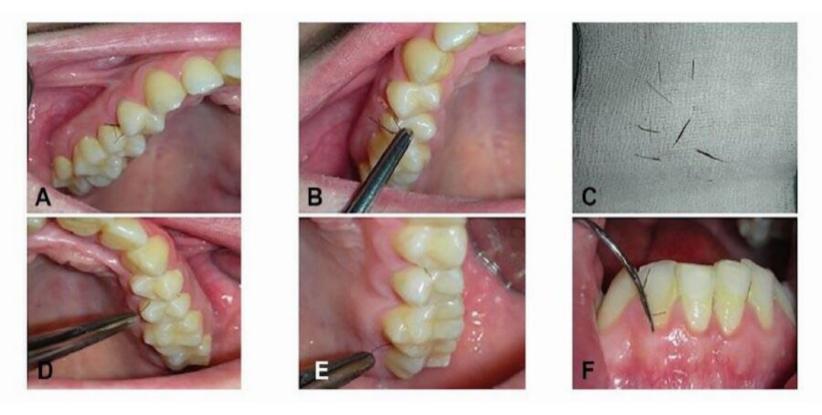

他们的发现发表在《口腔外科学、口腔医学、口腔病理学和口腔放射学》杂志上,记录了这名女子奇怪并反复出现的症状。2009年,她第一次寻求帮助,当时她的上门牙后面不断长出睫毛状的毛发。

医生诊断她患有多囊卵巢综合征,这是由性激素失衡引起的,可导致毛发过度生长。医生给她开了避孕药来调节激素水平,并给她做了口腔手术来去除牙龈上的毛发。

这位当时25岁的女子在毛发长出来之前已经停止服用避孕药,所以医生们只是像以前一样采取了*管双**齐下的方法:医生给她开了药物来平衡她的激素水平,还给她做了手术,并让她一年后再来。但在接受这些治疗后,她的牙龈长出了更多的毛发。

由于这是一种罕见的情况,医生决定利用她的情况,从她的牙龈中提取一小块组织样本。显微镜显示,长出毛发的牙龈组织异常厚。

这名女子正在服用避孕药来调节她的荷尔蒙,从而减少毛发的生长。她还做了头发切除手术。